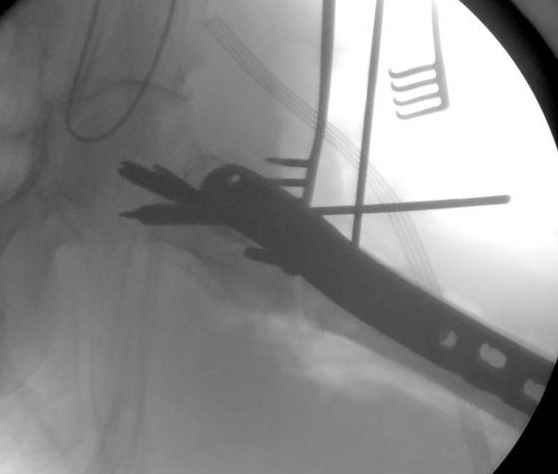

Применили проксимальную Synthes Locking plate, из-за множественных фрагментов посчитали более приемлемым в этом случае (клиника университетская, резиденты должны имет возможность созерцать разные варианты остеосинтеза).

Также старался минимизировать доступ на уровне перелома с субвастус доступом, диафиз фиксирован перкутанно, не стали гонятся за малым вертелом, как смог зафиксировал.

Перелом из четырех фрагментов, не стабильный (лекция Michael R. Baumgaertner, http://www.hwbf.org/ota/bfc/baumg/exp.htm), нужна стабильная фиксация.

Фиксация таких нестабильных чрезвертельных и reverse obliquity субтрохантерик переломов всегда была сложной задачей и ранее использовали Blade Plate. Но многие локальные общие ортопеды, к которым, в основном поступают такие больные, имели трудности с применением импланта, где необходимо было точная калькуляция по введению Blade и поэтому Synthes разработал Proximal Locking plate как альтернативу, где три проксимальные шурупа в разных направлениях создают концепцию угловой стабильности Blade Plate.

Со второго дня движения в суставе, контрольный осмотр через две недели и в зависимости от рентгенологического сращения, дозированную нагрузку с постепенным увеличением начнем через 5-6 недель.